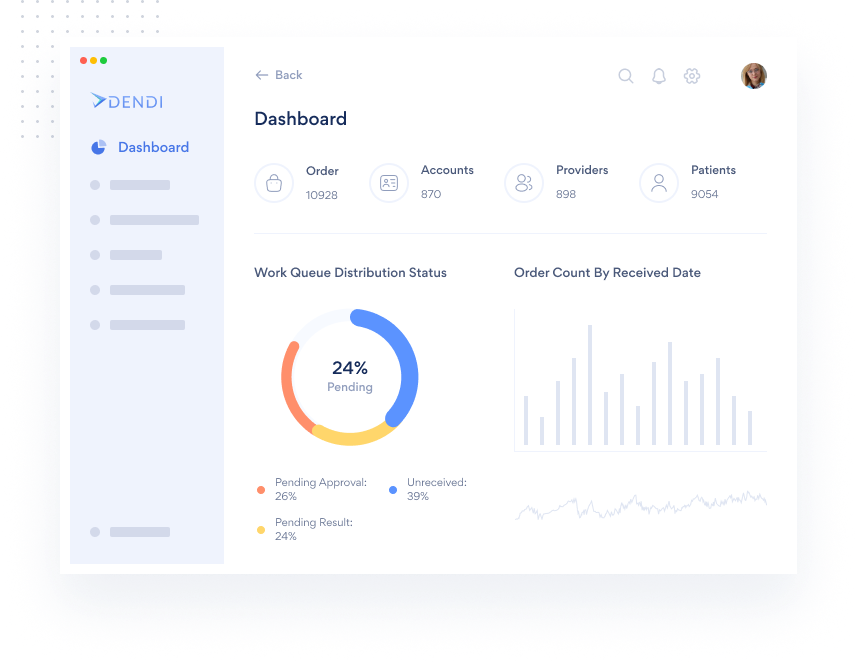

The only constant in healthcare is change. Dendi’s powerful

and user-optimized software platform equips clinical labs

with the tools needed to move forward with confidence.